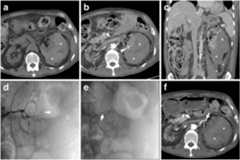

Fig. 1.

A 76-year-old female with several comorbidities, including hypertension, type II diabetes, epilepsy and chronic anaemia, suffered from severe pain and tenderness in her left lower abdomen. Features consistent with acquired cystic renal disese (ACKD) were noted in a magnetic resonance (MR)-cholangiopancreatography study (a) performed a few months earlier, including several moderately-sized cysts (thin arrows). Despite worsening end-stage renal disease (ESRD), she was not on haemodialysis and received antithrombotic prophylaxis after a previous deep venous thrombosis. Laboratory assays revealed a mild haemoglobin (8.2 g/dl) drop compared to baseline. At emergency department admission, an unenhanced multidetector CT study (b) was requested to investigate suspected acute diverticulitis. After detection of large left-sided subcapsular haematoma (*), a CT study was completed with contrast medium (CM) injection. Corticomedullary (c,d) and nephrographic (f) phase images showed the haematoma (*) exerting severe compression on the renal parenchyma, largely replaced by cysts (thin arrows) with mural discontinuity. Complemented with angiographic maximum-intensity projection (MIP) reconstructions (e), CT visualized small foci of CM extravasation isoattenuating with the blood pool (arrowheads). During renal arteriography (not shown), active bleeding was not observed anymore, indicating its spontaneous cessation. The patient slowly recovered during intensive care unit hospitalization, including blood transfusions and correction of metabolic acidosis